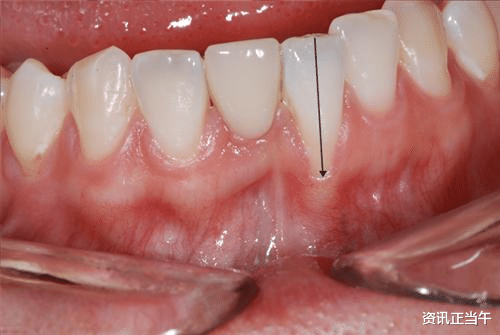

牙龈萎缩指的是牙龈组织的退缩和消失 。

正常情况下 , 牙龈应该完整地覆盖牙齿的根部 , 保护着牙槽骨和牙根 。

当牙龈组织受损或退缩时 , 牙根就会暴露在外 , 导致牙齿看起来变得更长 , 同时也增加了牙齿的敏感性和易感染性 。

牙龈出现明显的退缩 , 牙齿的根部会逐渐暴露在外 , 使得牙齿看起来变得更长 。